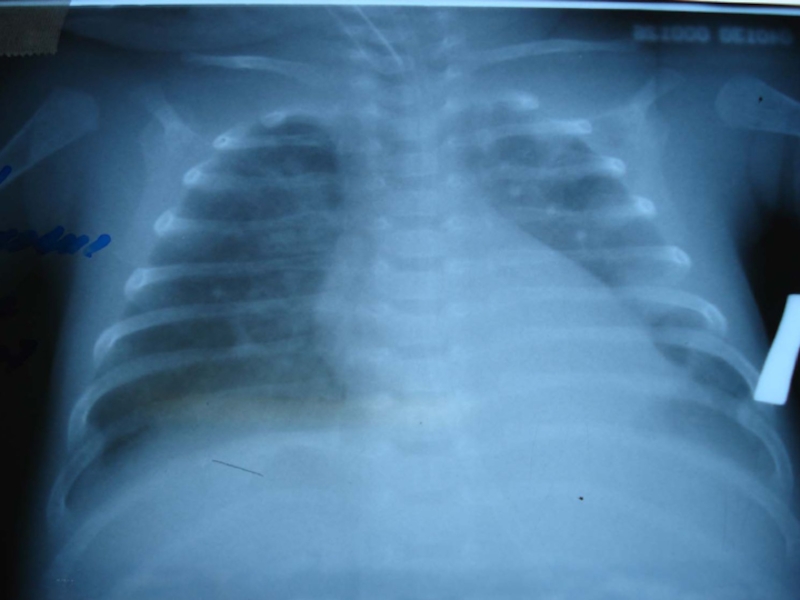

Глубина стояния ЭТТ должна уточняться Rö-графически

ВСЕГДА

Размер ЭТТ у новорожденныхГлубина стояния ЭТТ должна уточняться Rö-графическиВСЕГДА